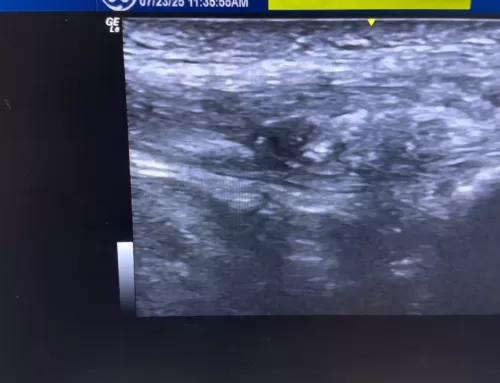

However, deeper ultrasound imaging reveals a prominent bony bump, known as insertional Achilles tendinopathy, which is the true source of the patient’s pain and swelling. The affected heel shows irregular bone structure, hypoechoic (dark) areas, and localized inflammation right at the pain point.

The comparison with the other (non-painful) side shows only minor tendon changes, confirming that the extra bone and tendon irregularity at the insertion point is the root cause of discomfort. This video is a great resource for understanding less obvious causes of heel pain and how ultrasound imaging can reveal hidden structural issues often missed in a surface-level exam.